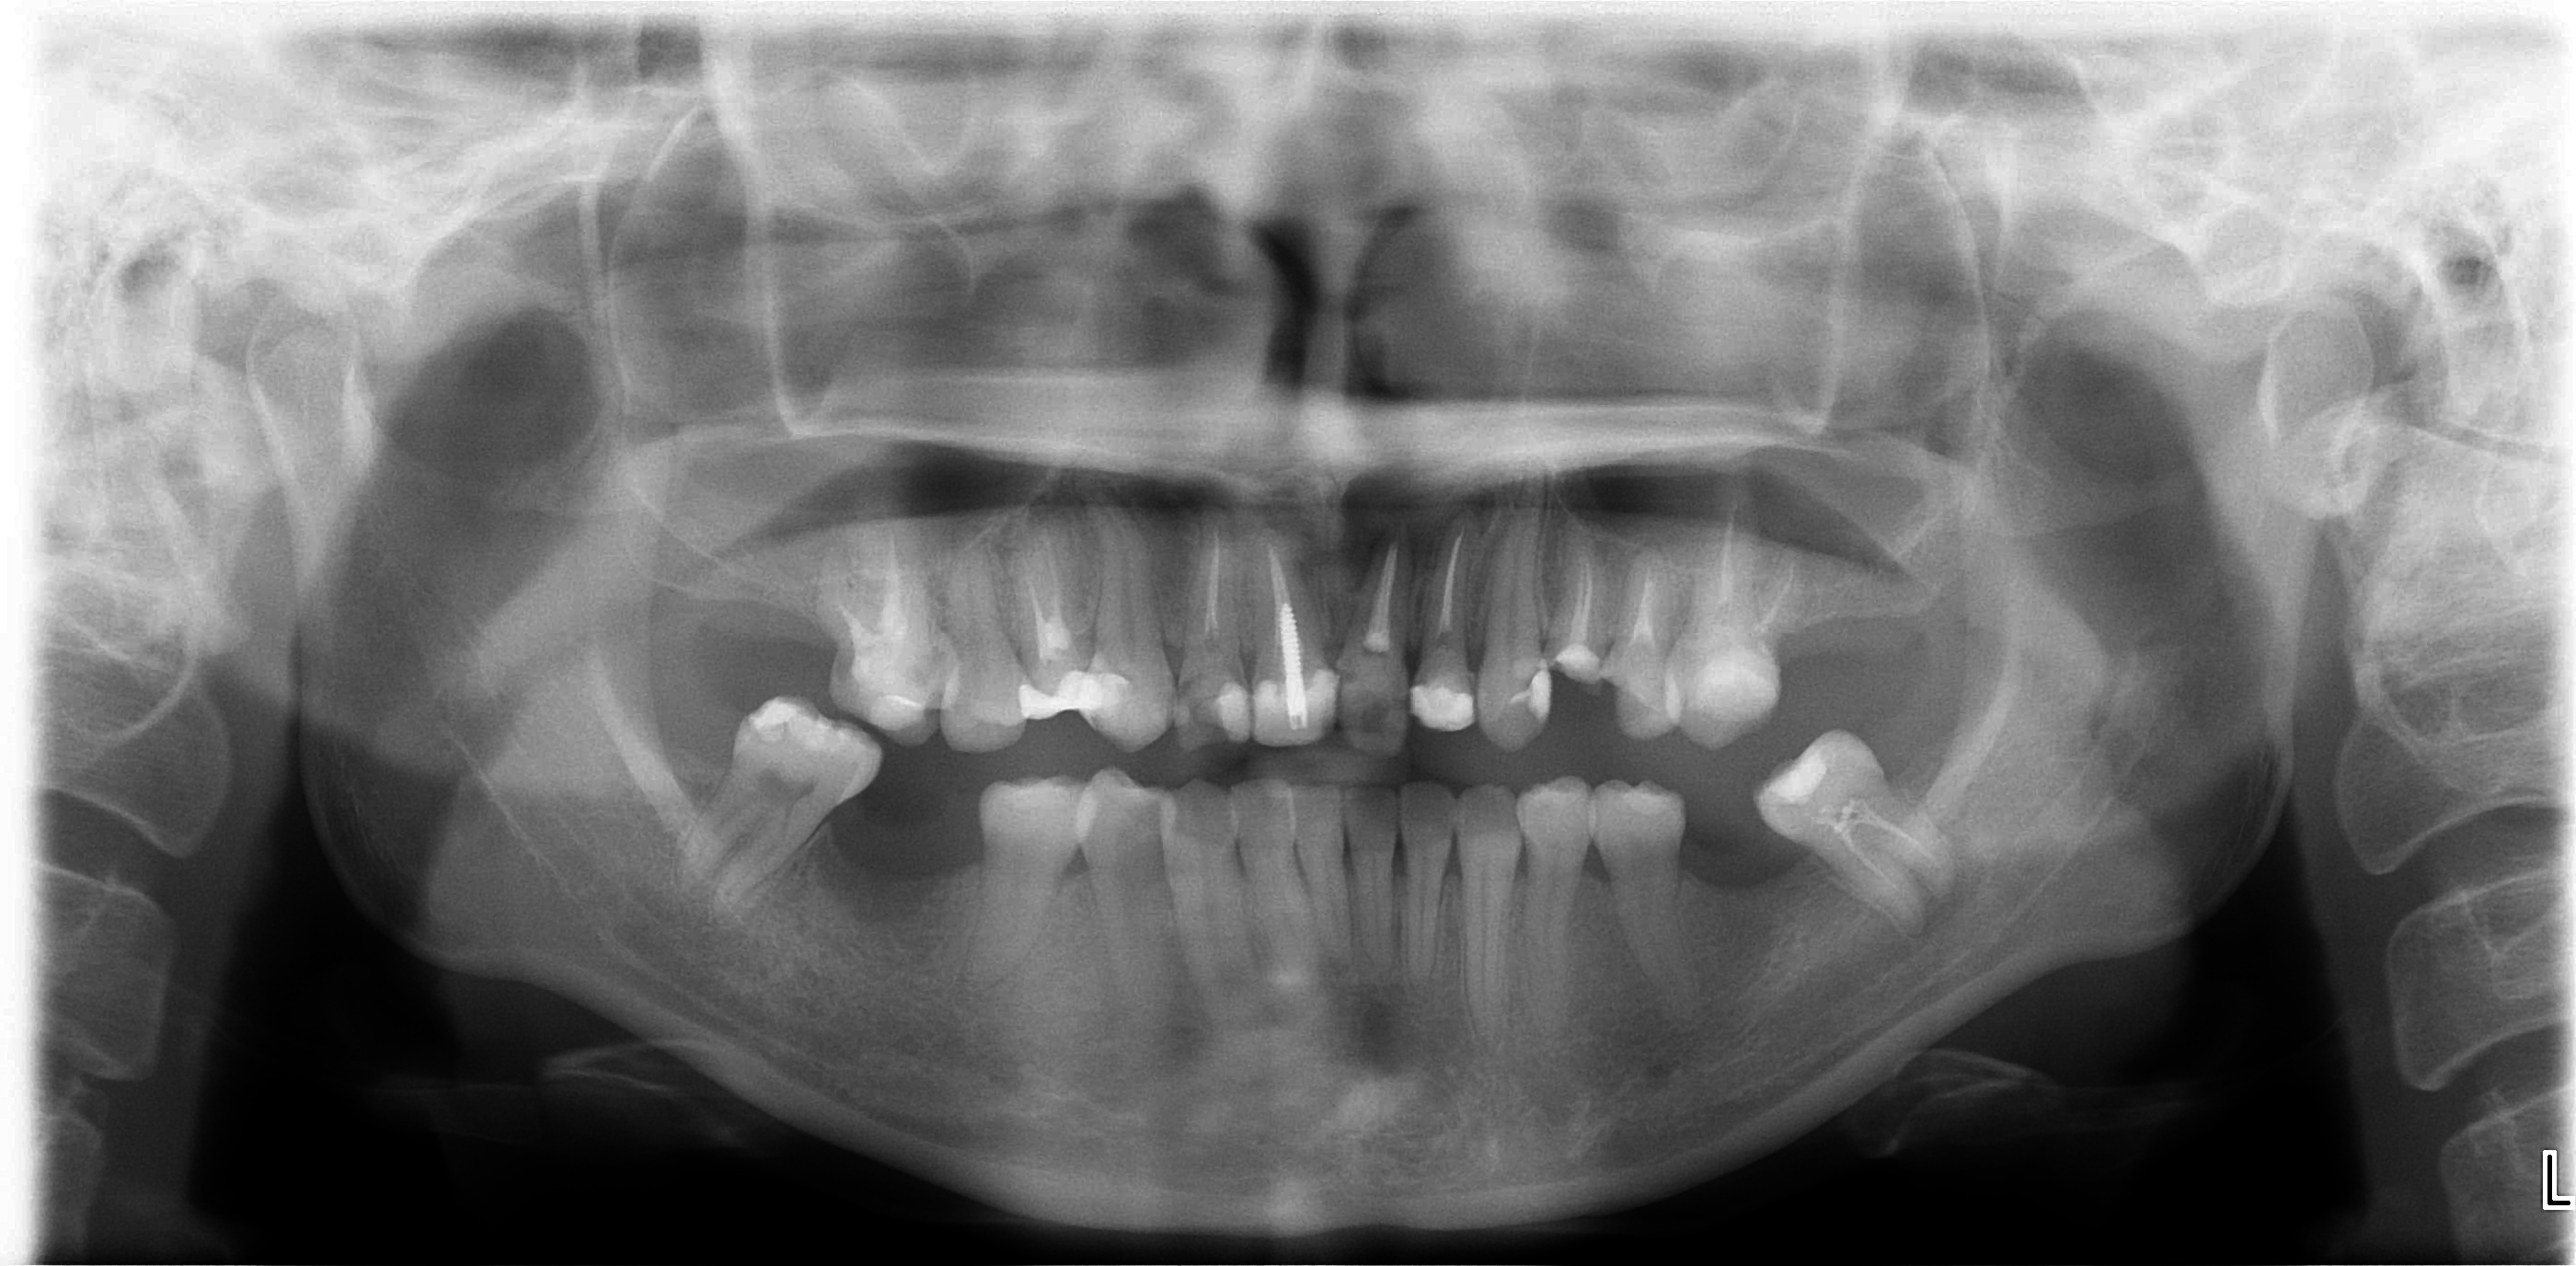

患者的經過診斷,問題如下:(圖二)

一、上頷右上第四小臼齒到左上第五小臼齒皆有不良補綴物,須移除。

二、部分前牙根尖病變 , 根管治療須重新完成 .

三、以假牙方式改變前牙外型

圖二 |